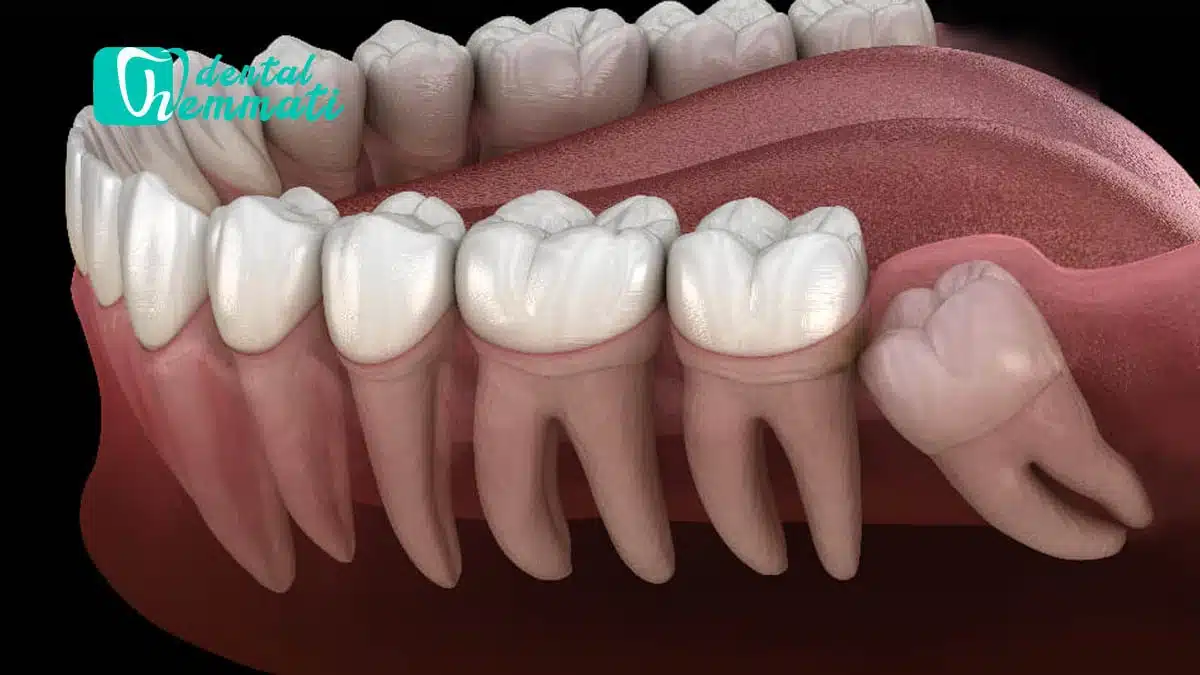

۲. رشد ناقص یا نهفتگی دندان

زمانی که دندان عقل نتواند به طور کامل از لثه بیرون بیاید، به آن دندان نهفته گفته میشود. دندانهای نهفته معمولاً باعث التهاب و تورم لثه میشوند و میتوانند منبع درد مزمن یا گاهبهگاه باشند.

در برخی موارد، رشد آن باعث حرکت و نامنظم شدن دندانهای دیگر میشود. این فشار به دندانهای کناری ممکن است موجب درد و ناراحتی شود، بهویژه در ناحیه فک پایین.

۲. ایجاد فشار بر دندانهای دیگر

اگر دندانهای عقل باعث فشردگی یا حرکت دندانهای دیگر شود، ممکن است نیاز به کشیدن آن باشد تا از ناهنجاریهای فکی-دندانی جلوگیری شود.